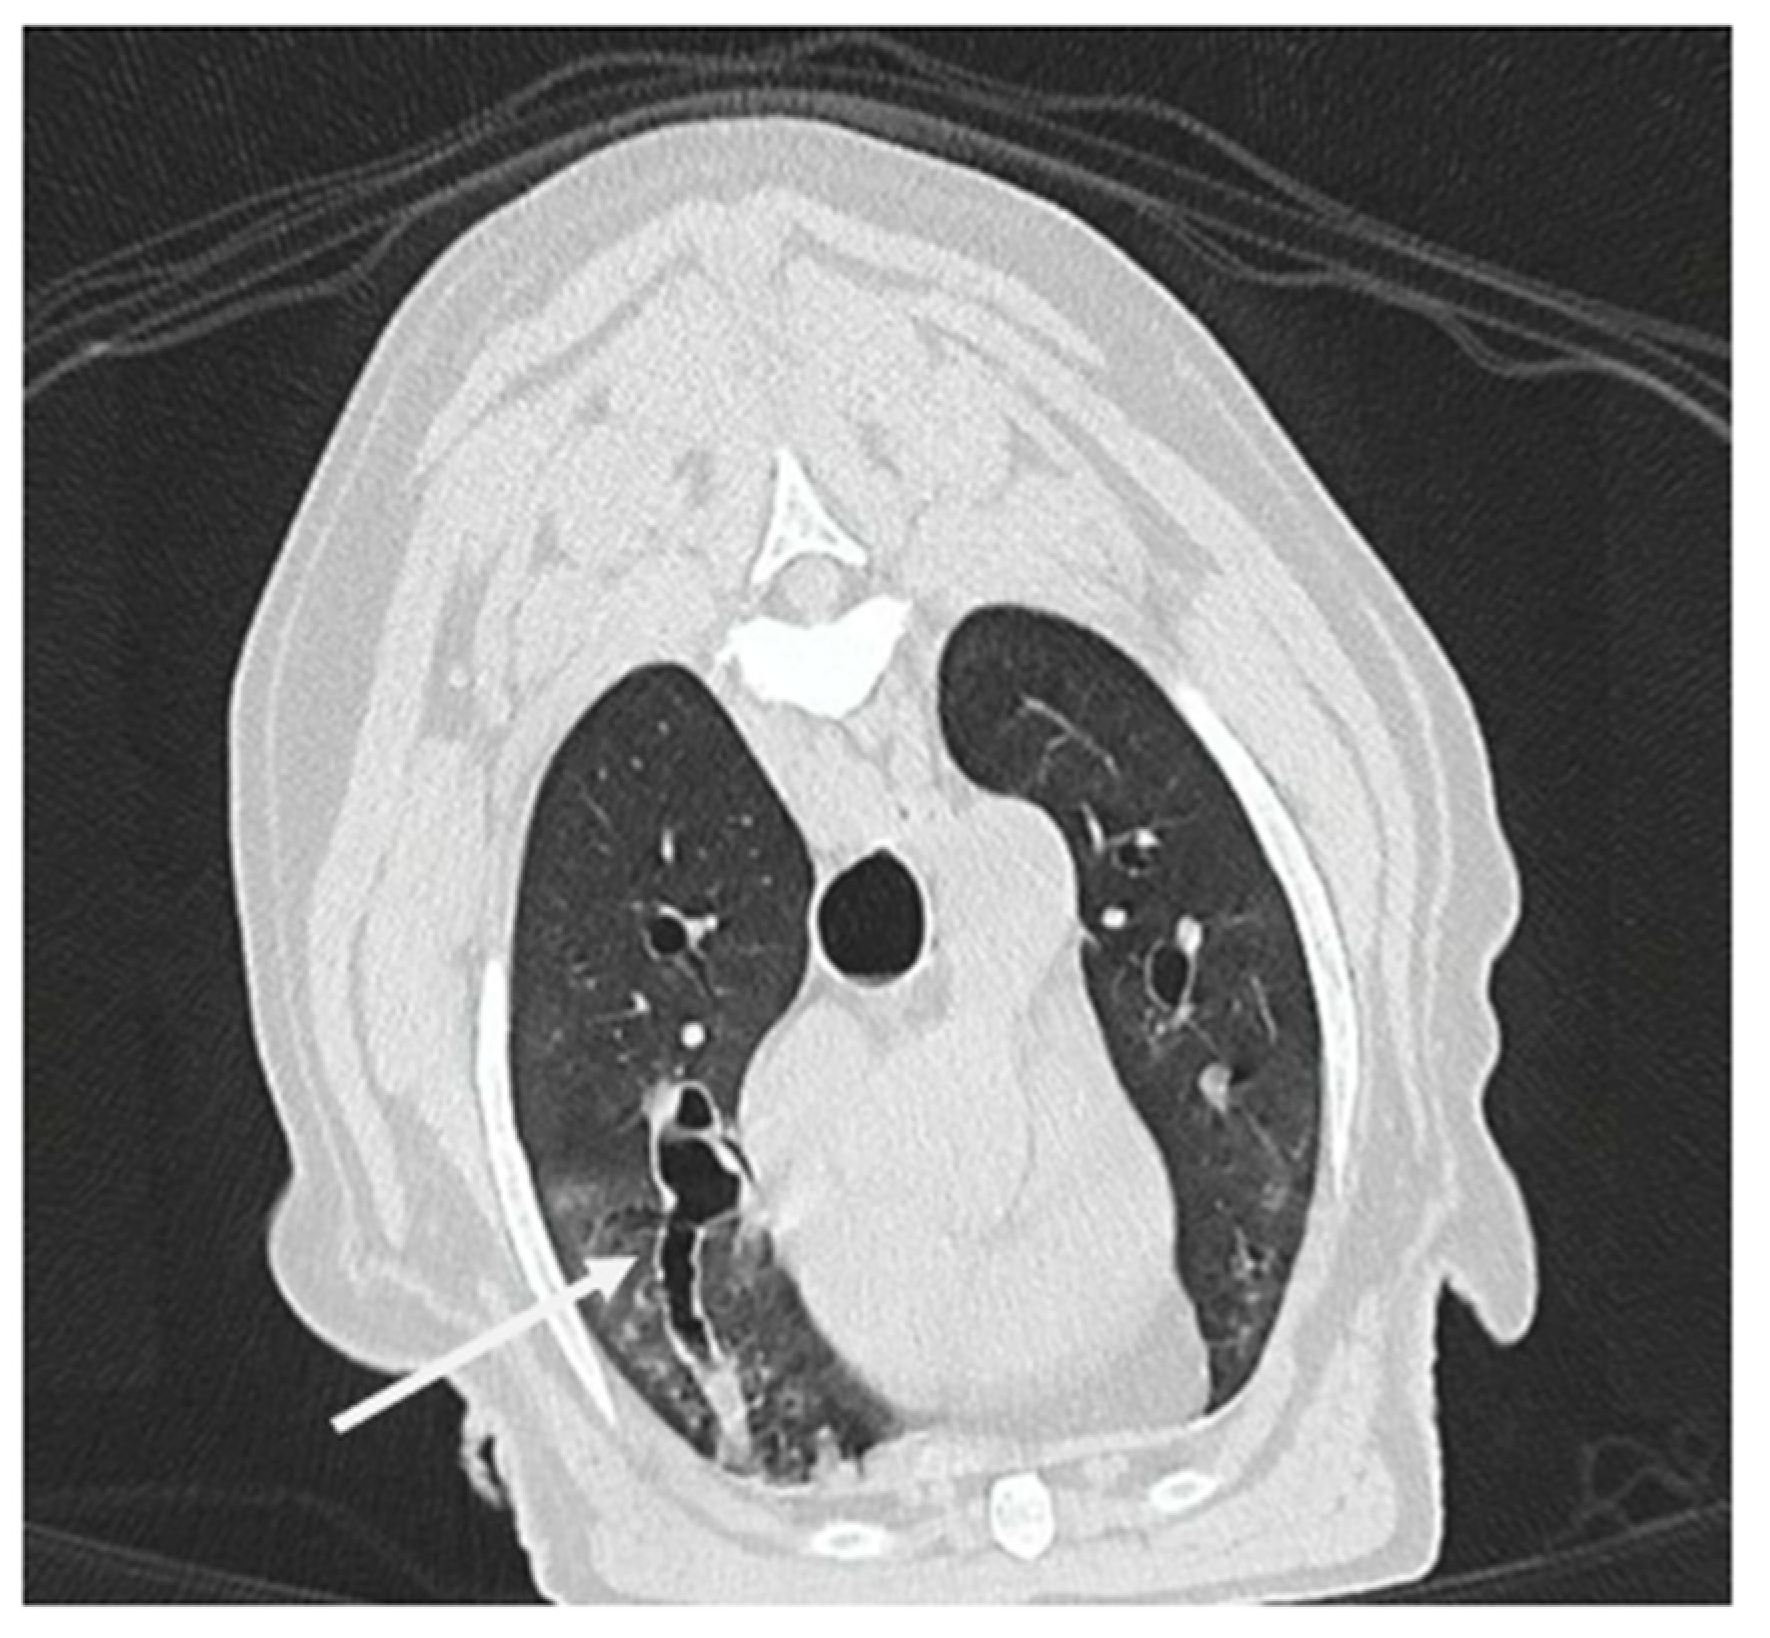

3.1.8. Computed Tomography Findings

3.2.2. Thoracic CT Versus Endoscopy